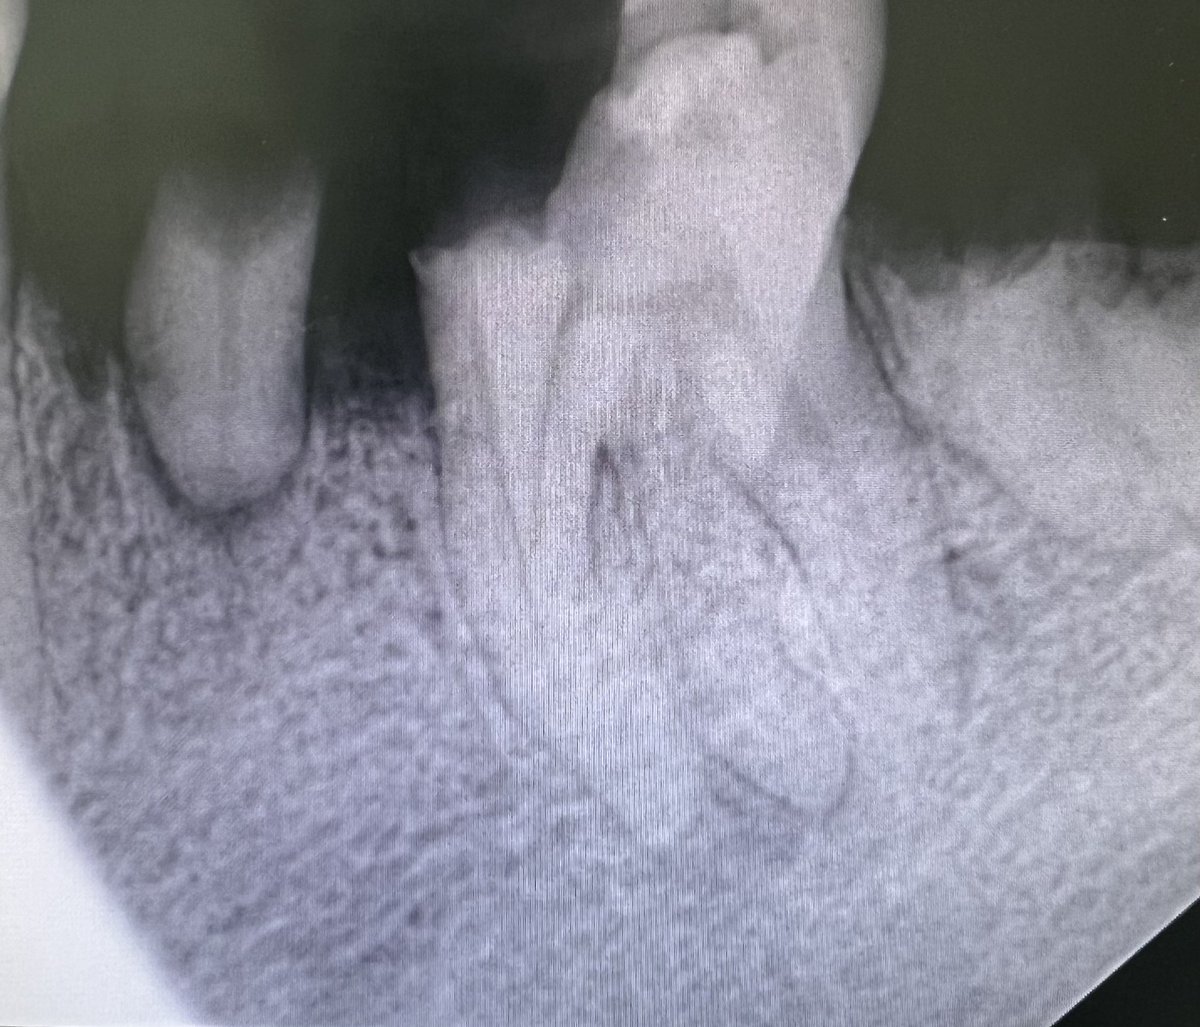

Zirconia crown on Endotreated #47 Implant supported crown on #46, The implant was placed by @alomar_ahmed